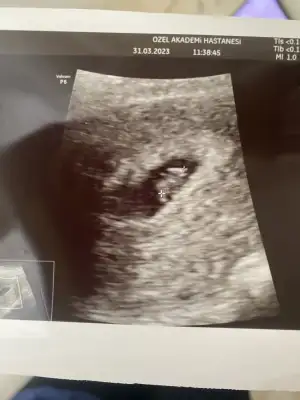

keseye göre tahmin yapan birileri vardıııı 7+5

Eklentiler

• 06169376-19D5-486F-8187-FAE3BEFBABD4.webp

06169376-19D5-486F-8187-FAE3BEFBABD4.webp

26,6 KB · Görüntüleme: 81